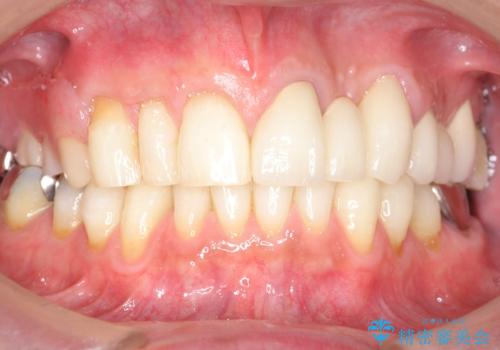

牽引により歯の保存が可能となり、ブリッジによる補綴を行うことができました。

健全歯質を歯肉縁上に出すためにしっかり挺出させたことで歯根長が短くなりましたが、仮歯で十分に保定した結果動揺度Ⅰ程度となり、ブリッジの支台歯にすることが可能と判断しました。

患者様には「抜歯適応の歯を残せて嬉しいし、とても丁寧に治療して頂けた」と大変喜んで頂けました。

クラウンの種類:オールセラミッククラウン スタンダード